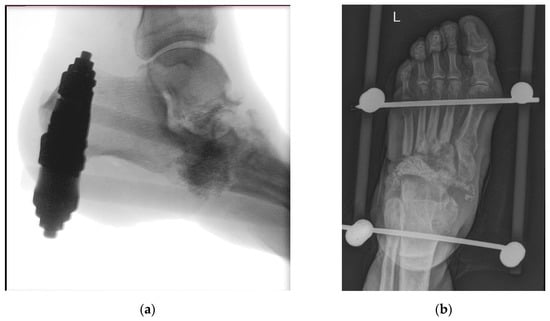

Out of the four cases in this group, three were reported to have Charcot neuroarthropathy and all had confirmed septic osteoarthritis. Table 1 shows their detailed characteristics, including significant concomitant diseases documented. In three cases, the procedure was single-phase with resection of affected midfoot bones, debridement of soft tissue, and placement of BAG granules; in one case, the procedure was two-phase, involving the placement of antibiotic beads and, in the second phase, BAG was applied instead of antibiotic beads. Figure 2 displays an example of a single-phase procedure with extensive resection of the midfoot bones due to osteitis. At least three weeks of intravenous antibiotic treatment was received in the perioperative phase. In three cases, an external fixator was used. None required revision during the 30-day period postoperation or suffered early complications. Additionally, no late complications in terms of recurring osteomyelitis or septic osteoarthritis requiring operative management were observed.

Figure 2.

(a) Intraoperative X-ray—resection of cuboid bone, base of 4th and 5th metatarsal bones as well as head of talus due to osteitis, placement of bioactive glass granules, and an external fixator. Image captured intraoperatively with diascopy using Siemens Cios Alpha® (Siemens, Munich, Germany) (average exposition parameters: 52 kV, 0.03 mAs, and 7.5 fps); (b) patient three months after resection and bioactive glass insertion. Image captured with Philips Digital Diagnost® (Philips, Amsterdam, The Netherlands) (exposure parameters: 63 kV and 2 mAs).